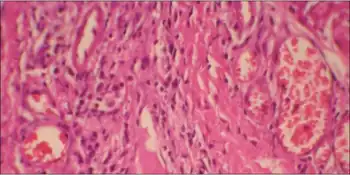

Torso of thirty-seven-year-old, second-generation patient, exhibiting lentiginosis.